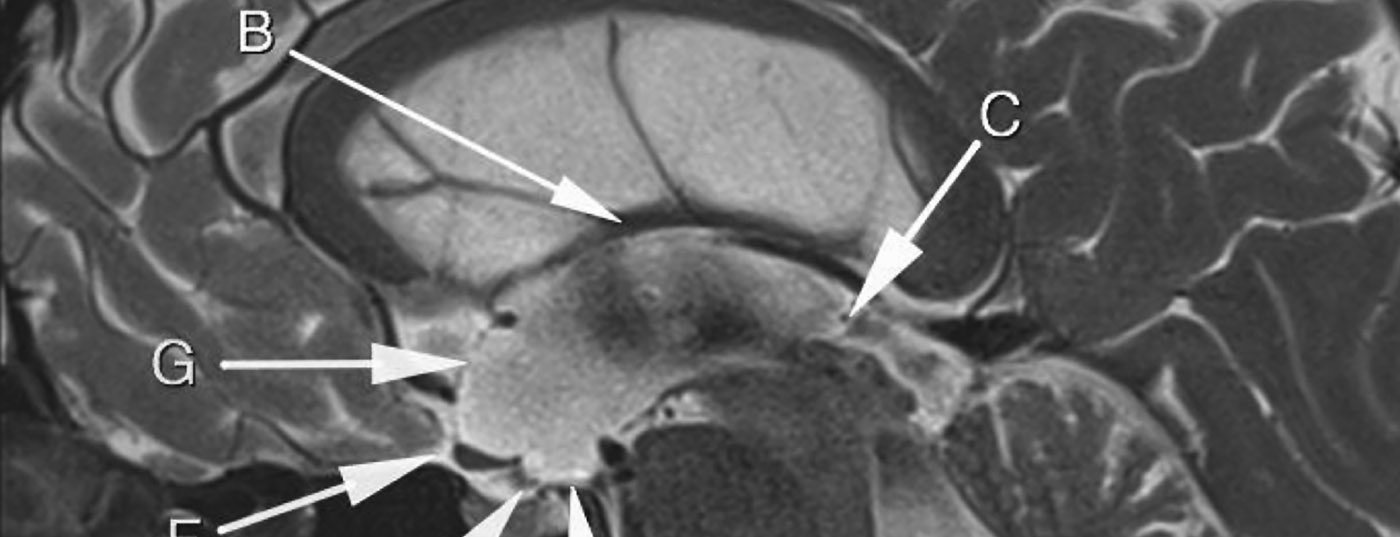

Fallbeschreibung: Wir berichten über einen 43-jährigen Patienten, der im Sommer letzten Jahres einen erstmaligen Krampfanfall erlitten hatte. Die umfangreiche Epilepsieabklärung ergab keine epilepsietypischen Potenziale. Im Rahmen der weiteren Abklärung zeigte sich aber im MRT als Zufallsbefund ein deutlicher Hydrocephalus occlusus bei proximaler Aquäduktstenose.